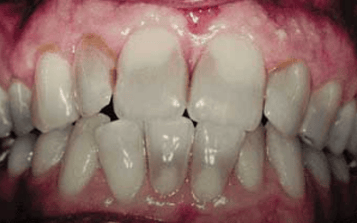

Fourth degree: Intense pigmentation combing very dark stains with highly pronounced bands4 (see Figure 1)

Degrees of discoloration are based on the extent and degree of use.

First degree: Light yellow, grey, or brown. Confined to incisal three-quarters without banding

Second degree: Darker and more uniform discoloration without banding

Third degree: Very dark blue or grey with banding4